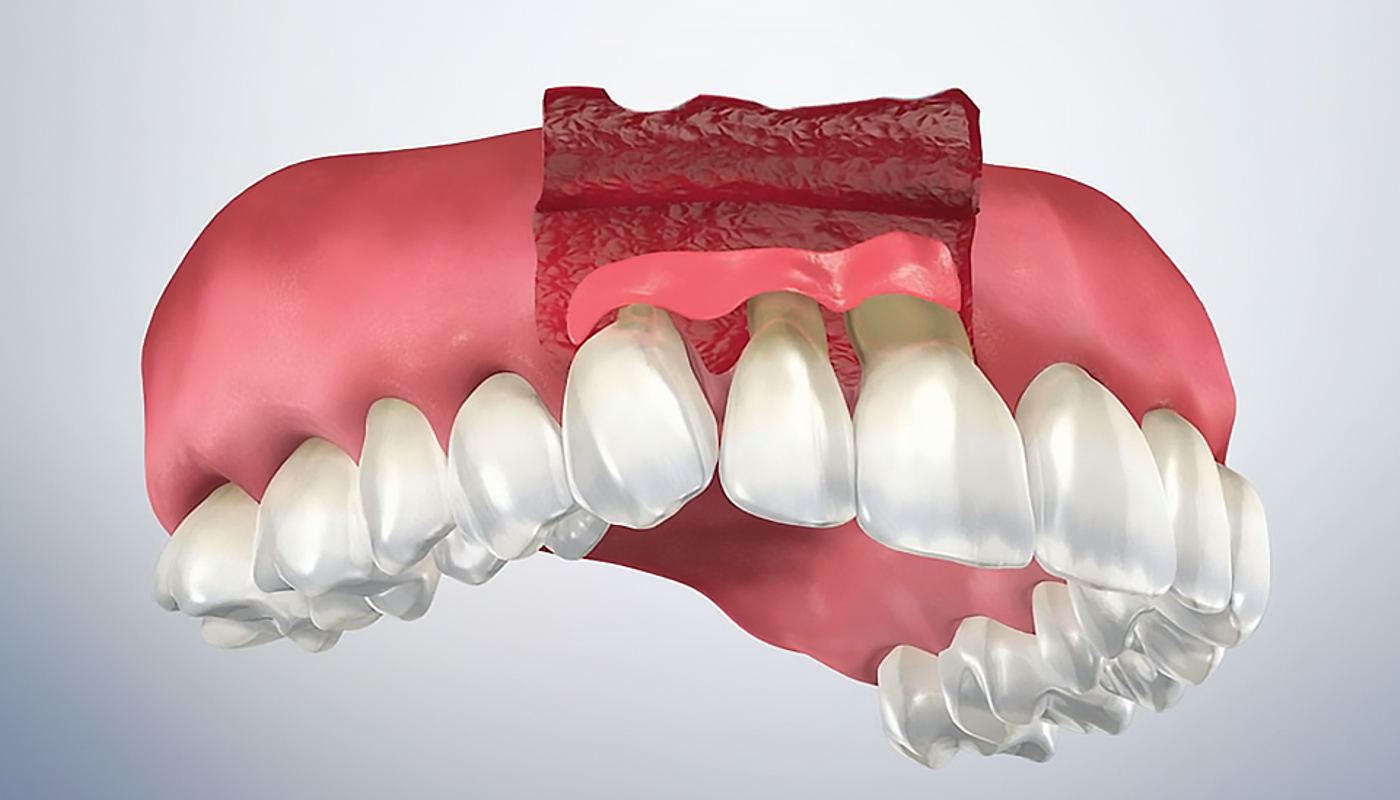

Chirurgia mucogengivale

La chirurgia mucogengivale è una branca dell’odontoiatria che si occupa di correggere difetti gengivali e migliorare l’estetica e la salute delle gengive. Nel nostro Studio dentistico...